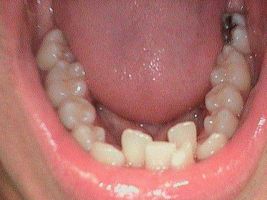

Full Mouth Rehab

Before

After